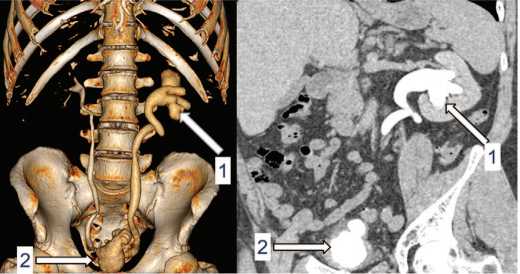

снижение объема мочевого пузыря до 50 мл, утолще ние его стенок до 10мм.По данным компьютерной то мографии (КТ) органов дыхания картина диссемини рованного туберкулеза легких (рис. 1). На КТ органов брюшной полости с контрастным усилением двухсто ронняя уретероэктазия, более выраженная слева, мик роцистис, утолщение стенок мочевого пузыря (рис. 2) КТ головного мозга выявила мелкие гиперваскулярные очаги в левой гемисфере (рис. 3).

Рис. 1. Больной Ж. КТ органов грудной клетки: диссеминированный процесс в легких, киста правого легкого

Fig. 1. Patient J. Сhest CT: disseminated process in the lungs and a cyst in S1 of the right lung